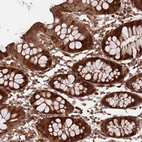

Immunohistochemical staining of human colon shows strong cytoplasmic and nuclear positivity in glandular cells.